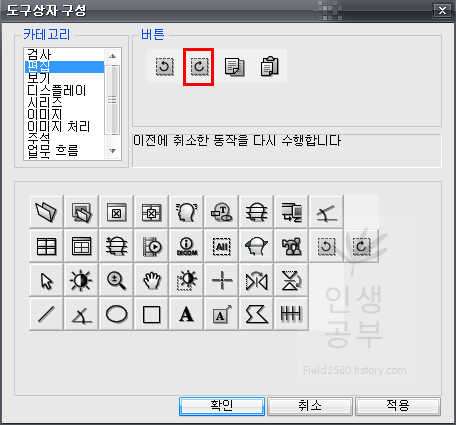

그 후에 2번째 칸에 있는 이전에 취소한 동작을 다시 수행합니다 버튼을 추가해줍니다.

두 번째 버튼을 클릭하고 아래로 드래그해서 내려주면 아래 도구상자에 추가됩니다.참고로 위의 두 버튼은 단축키를 알아두시면 훨씬 편하게 사용하실 수 있습니다. 단축키가 익숙해지면 도구상자 메뉴에서 삭제해도 상관없습니다. 하지만 익숙해지기 전까지는 도구상자 메뉴에 넣어두시는 걸 추천해 드립니다.